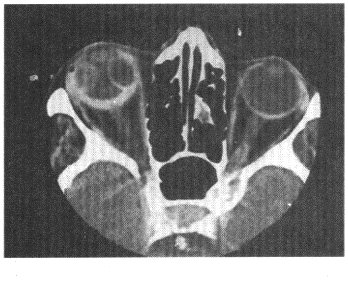

10.男,右眼外傷后視物不清,CT掃描如圖所示,正確的描述或診斷是

正確答案:ABCD 解題思路:圖示右側眼環增厚,密度增高,眼球外側密度增高影及內側類圓形低密度影,視網膜區可見稍低密度影,綜合患者病史考慮為右側玻璃體出血及視網膜剝離,故ABCD正確。